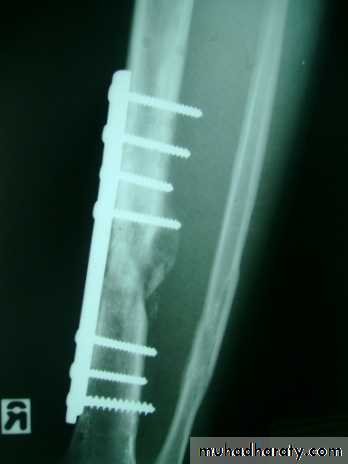

Operative treatment:

Indicated mainly when the fracture cannot be reduced adequately by manipulation, or when plaster alone fails to maintain an acceptable position of the fragments.Closed intramedullary nail or Plate and screws used commonly.

Fixations of fractures tibia and fibula